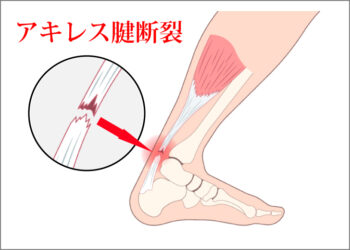

アキレス腱断裂

アキレス腱断裂は、腱が部分的または完全に切れてしまう状態です。

・突然「バチン」と音がして、かかとに力が入らない、走れない、ジャンプできないといった症状が出る

・急性で強い痛みを伴い、腫れやつっぱり感が現れる

アキレス腱断裂

・突然「バチン」と音がしてかかとに力が入らない

・歩行やジャンプが困難

・急性の強い痛み、腫れ、つっぱり感が現れる